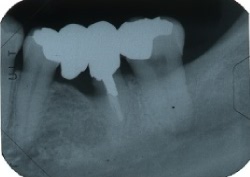

●黒く写っているのが上顎洞です。

このままでは、上顎洞までの距離が短く、インプラントができません。

●人工骨を填入して骨を作ります。

●骨ができたら、インプラントの処置を行います。

●上顎洞までの距離が短く、このままではインプラントができません。

●インプラント周囲に骨を作る事によって、インプラントができます。